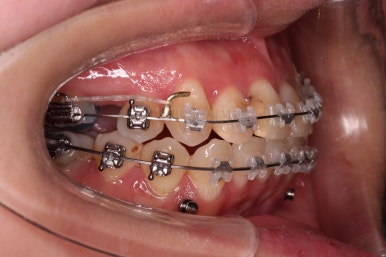

옆모습 중간중간 체크해 주고요.

이번 환자분은 옆라인이 애초에 매우 좋으셨기 때문에 입매를 바꾸지 않아야해서 오히려 더 세심한 치료가 필요한 환자분이셨습니다.

교합이라던가 부족한 부분을 좀 더 마무리하고요.

마무리 못한 어금니 치료와 앞니 심미보철을 마무리 합니다.